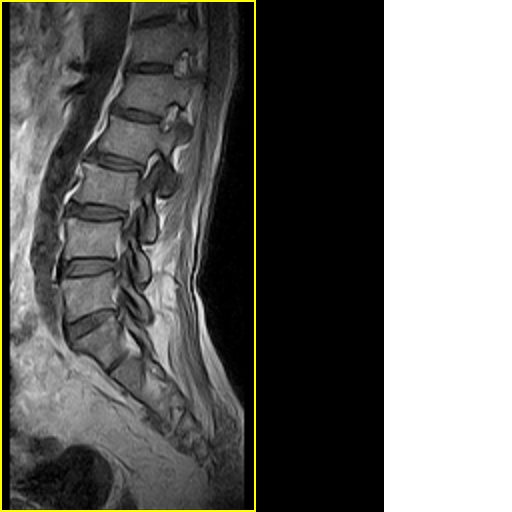

标题: MRI0859:[原创]腰椎,男,78岁,右下肢跛行两月 [打印本页]

男,78岁,右下肢跛行两月.

腰间盘膨出、黄韧带肥厚、可疑先天性腰椎管狭窄。

退行性骨关节病:增生、椎间盘变性、膨出...

退行性病变:增生、椎间盘变性、膨出[l4-5、l5-s1 椎间盘膨出]